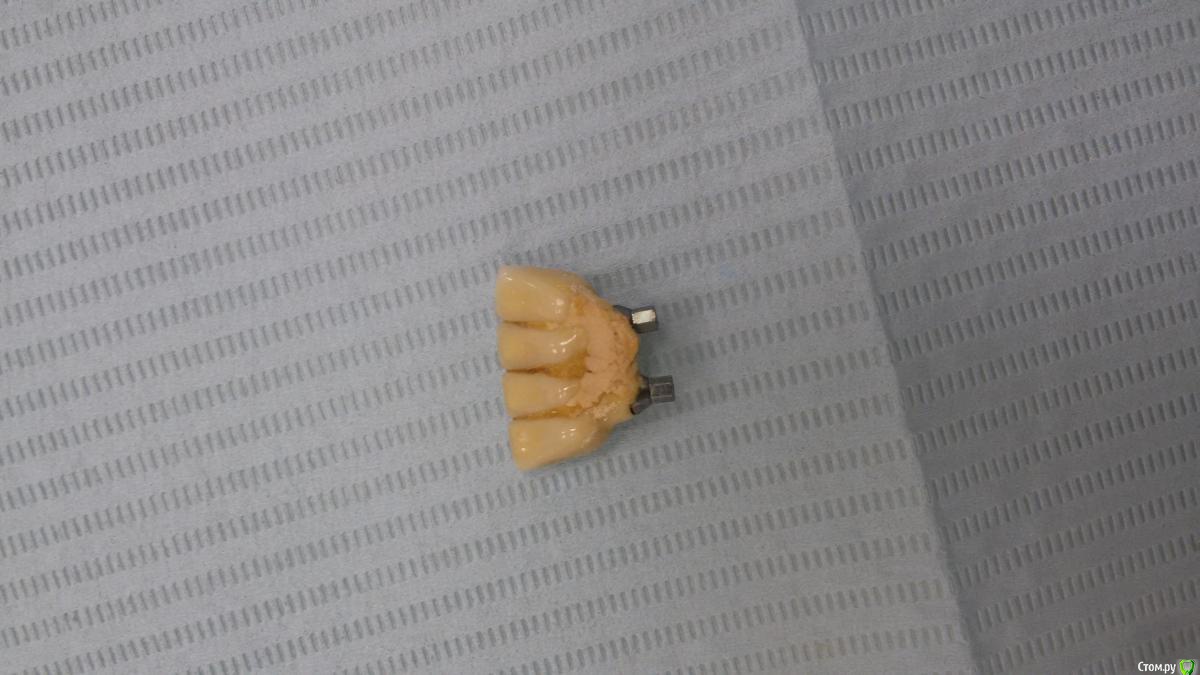

Бандерлога Опубликовано 20 сентября, 2016 Поделиться Опубликовано 20 сентября, 2016 Сломалась ортопедическая конструкция. Имплантаты повреждены, надо удалять. Обломки винтов из шахт достали.1 - Посоветуйте как деликатно удалить имплантаты. 2 - как Вы думаете, какая система? Ссылка на комментарий